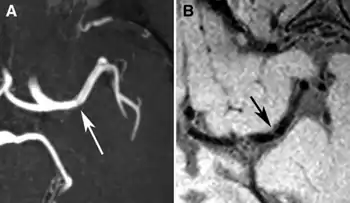

a,b)Individual swith a left partial anterior circulation infarct caused by a left middle cerebral artery (MCA) stenosis